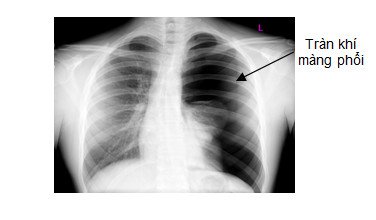

4.1. Tai biến tràn khí màng phổi

Tai biến tràn khí màng phổi sau khi đã lấy được bệnh phẩm thường xảy ra ở những bệnh nhân cao tuổi; bệnh nhân có thể trạng gầy, thành ngực mỏng; mắc bệnh COPD; bệnh nhân đang thực hiện sinh thiết bị ho,...Nếu bệnh nhân bị tràn khí màng phổi ở mức độ ít sẽ tự hết, còn nếu tràn khí nhiều cần phải dẫn lưu màng phổi cho bệnh nhân.